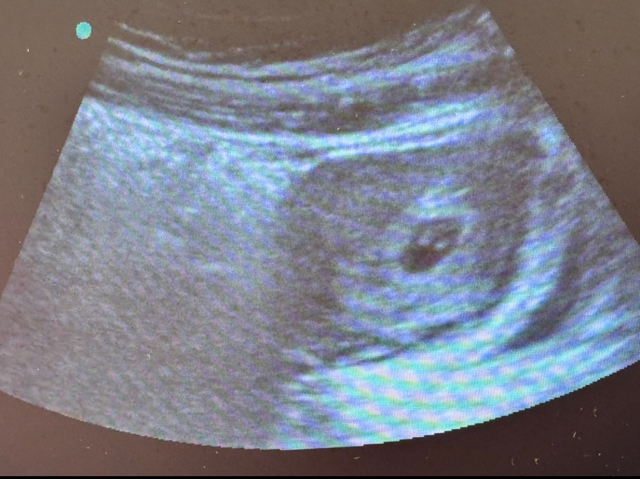

I’m 7 weeks and 1 day pregnant and I’m bleeding I’ve been bleeding on and off from brown blood to pink to red with clots it’s been like this for a couple days. I got checked out and my levels went from 5,198 to 5,840. I think maybe subchorionic hematoma. I’m just scared because of my other losses also I’m not cramping unless I have to fart but other than that no pain